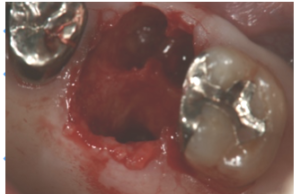

①抜歯後の状態です。何も処置しない場合は、3~5mm幅がなくなります。